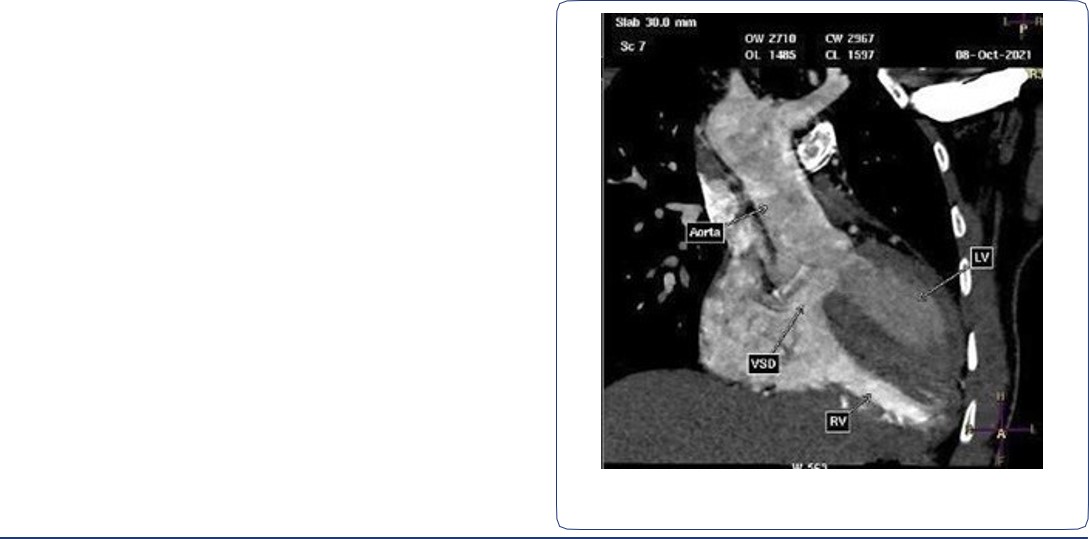

Two arterial supplies to the right lung arising from the descending aorta. A dominant one arising from the medial side that supplies the right upper lobe (Figure 3). Another smaller branch supplies the right middle and lower lobes (Figure 4).

Right ventricular dilatation with myocardial hypertrophy (Figure 4).

Figure 4: Contrast-enhanced CT chest axial and sagittal views, showing another small arterial supply to the right lung arising from the descending aorta. Dilated right ventricle with right ventricular wall hypertrophy.